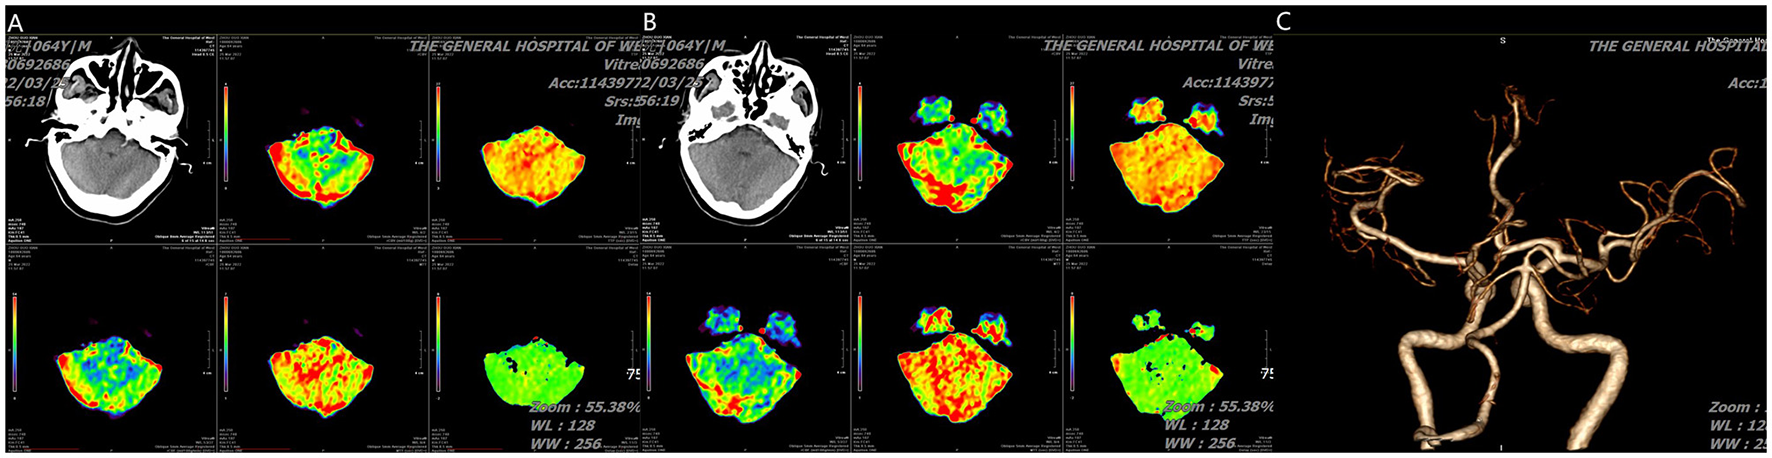

Figure 2

(A, B) CT perfusion show cerebellar infarction with small core infarction but large ischemic penumbra and (C) angiography (posterior-anterior view) show absence of right vertebral artery and normal basilar artery.